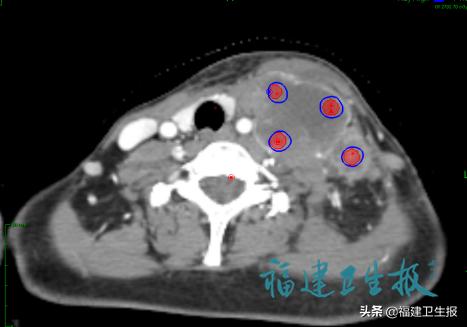

简单来说就是在 肿瘤内部设置一个个直径1~1.5公分、间隔1~2厘米的“球”, 运用射波刀的精准性,进行高剂量、高精准的“打靶”照射, 只照射这些虚拟的球, 取得了良好效果,同时因为射线只照射肿瘤内部, 病人没有明显的毒副反应。

3D-Lattice技术肿瘤内部高剂量照射区域分布图(蓝色)